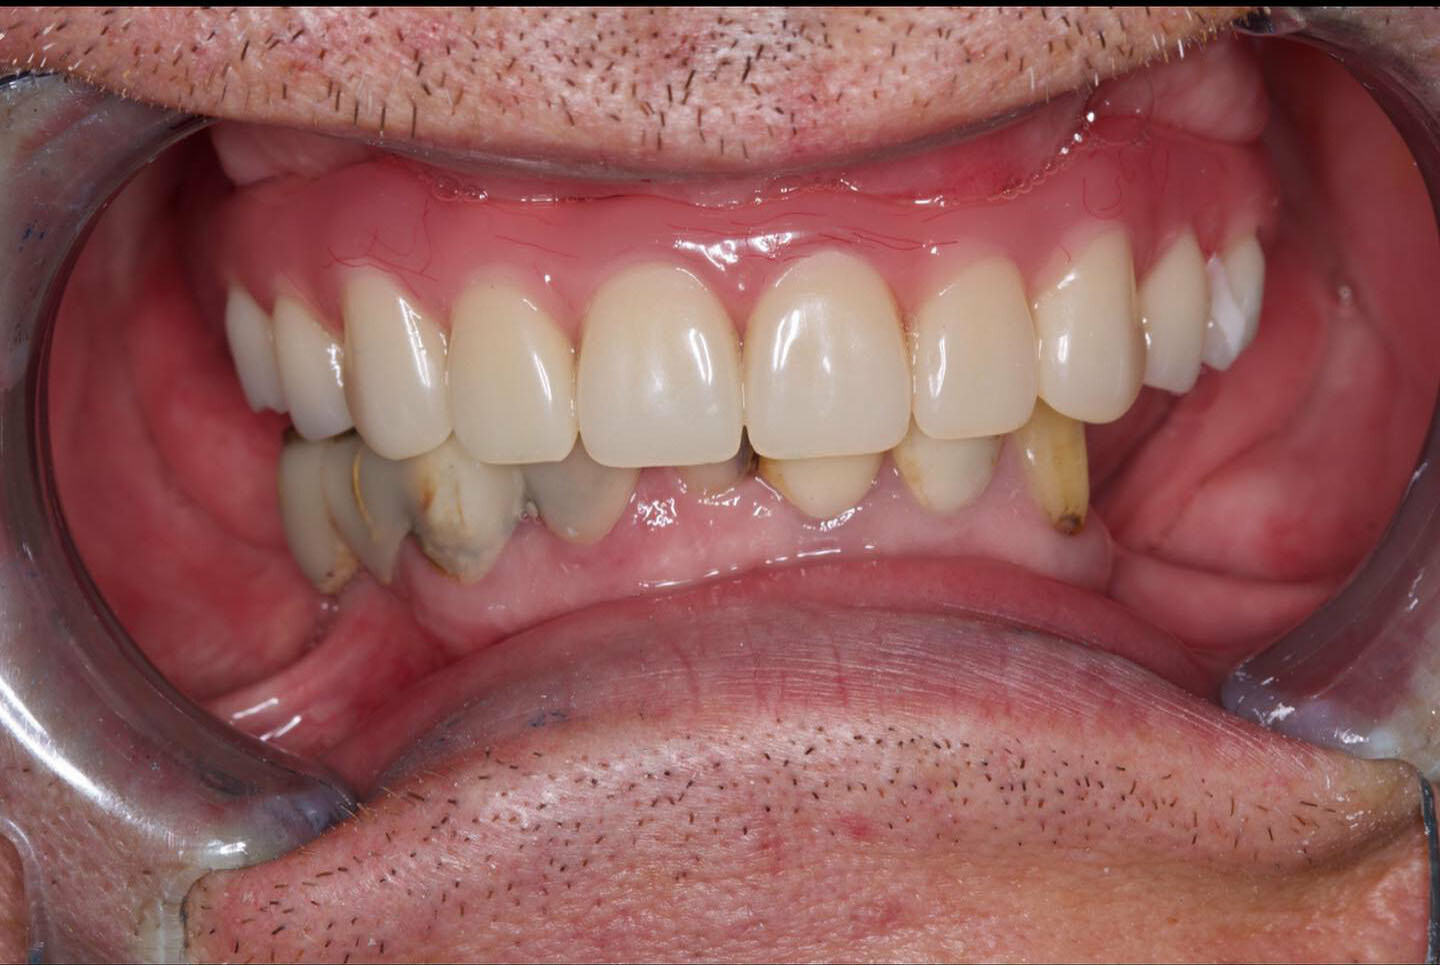

All-on-4 («все на четырех») - прогрессивный протокол имплантации челюсти на 4 имплантах, применяющийся для протезирования зубного ряда при его значительных дефектах (когда утрачено множество зубов) или в случае полной адентии. Начало методике было положено более 20 лет назад, когда первые попытки португальского врача П. Мало в данном направлении увенчались успехом. В имплантации All on 4 непревзойденный комфорт для пациента дополняется другим, не менее значимым аспектом – доступной стоимостью протезирования. |